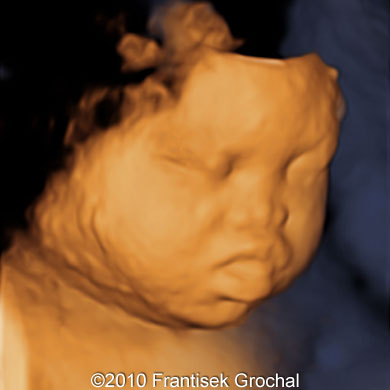

1.) Cleft Lip/Palate

Cleft lip is a gap in the upper lip, which can range in severity and where it is located.

On ultrasound, cleft lip is recognized by a notching in lip. While cleft lip can be isolated (the only abnormality the baby has), it can also be associated with micrognathia (a small jaw), cleft palate (a gap in the roof of the mouth), and a flattened face. Extra amniotic fluid around the baby can also be indicative of a cleft lip, due to the baby having difficulty swallowing properly

Due to these other possible abnormalities being present, we sonographers will pay attention to these other areas to rule out whether the baby has a syndrome (multiple abnormalities present) or if the cleft lip is an isolated finding.